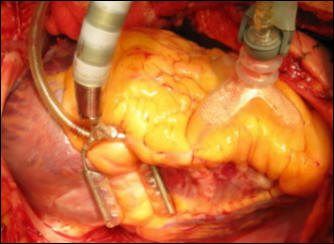

Рисунок 41. Этап коронарного шунтирования: формирование дистального анастомоза с

аутовенозным трансплантатом на остановленном сердце (Хубулава Г.Г., Пайвин А.А.,

Юрченко Д.Л.)